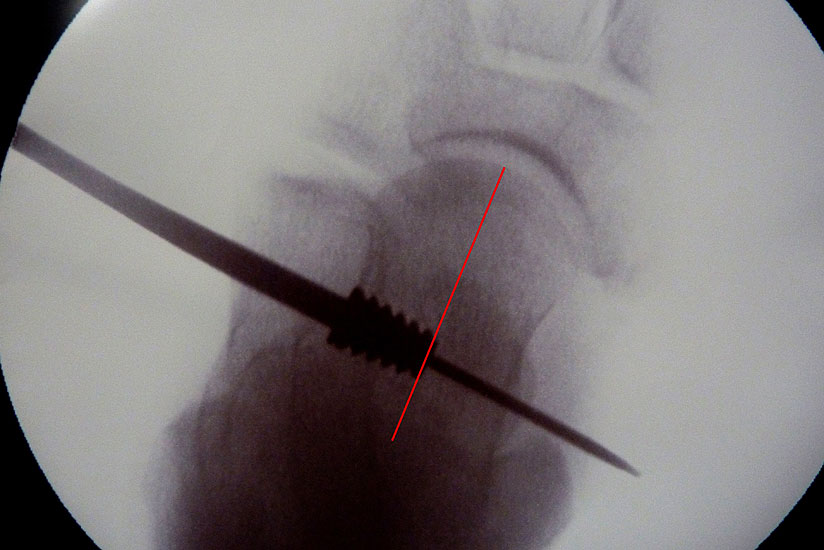

• Sehr sicheres Verfahren sobald der Führungsdraht im Sinus tarsi platziert ist. Das zugehörige Instrumentarium, alle Probeimplatate und auch das endgültige Implantat sind kanüliert und werden stets über diesen Guidepin geführt.

Abbildung 1

• ProStop Implantationssieb von Arthrex mit Führungspin, Probeimplantaten in aufsteigender Größe und lasermarkiertem Eindrehinstrument mit Handgriff (Abb.1).

• Bildverstärker.